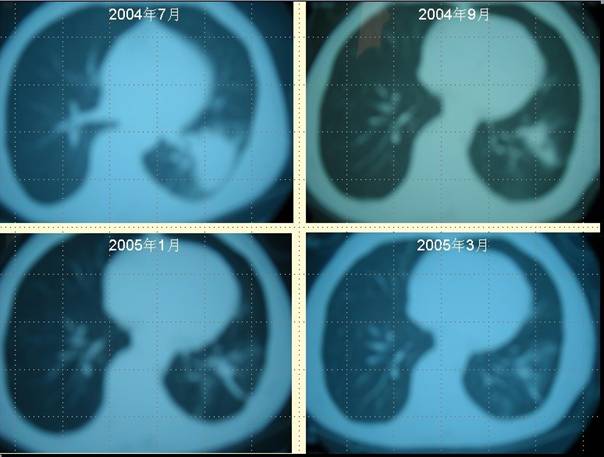

[提要] 案例二 柴XX的病理圖片 肺癌病人柴XX采用“董氏治癌法”治療前后 CT對照變化

肺癌病人柴XX采用“董氏治癌法”治療前后 CT對照變化